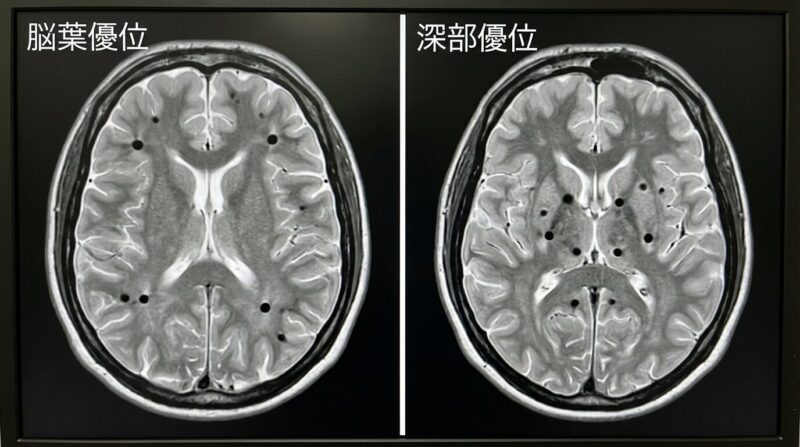

脳微小出血の分布パターン比較 — 深部型(基底核・視床)と脳葉型(皮質表面寄り)

左: 深部型(高血圧性)— 基底核・視床・脳幹に多い | 右: 脳葉型(CAA関連)— 大脳表面寄りに多い

パターン 起こりやすい場所(例) 背景(推定) 相談のポイント

深部型(deep) 基底核・視床・脳幹・小脳など 高血圧による血管の傷みが関与しやすい[3] 家庭血圧→目標設定→降圧の最適化(減塩・運動も)[8]

脳葉型(lobar) 大脳の皮質/皮質下(脳葉) CAAが関与することがある[4] 血液サラサラの薬の扱い、出血リスクの説明とフォロー[5]

混合型(mixed) 深部+脳葉の両方 複数の機序が混在することも 白質高信号・ラクナなども含めて総合的に管理[1]